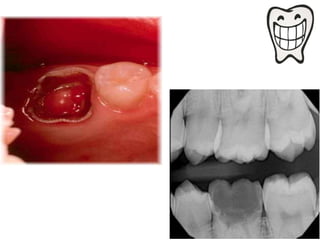

• The tooth with necrotic pulp may exhibit only

slight periradicular change, periradicular

bony lesion may accompany the necrotic pulp

Appear normal except for widening of PDL

space.

• Radiographical features:

Radiographical changes seen are limited to

only slight thickening of the periodontal

ligament space in apex region of the involved

tooth.

While in chronic periapical abscess,

radiograph often reveal small radiolucent

area at the root apex of the involved tooth

with poorly defined margins.

• The toothwith necrotic pulp may exhibit only slight periradicular change, periradicular bony lesion may accompany the necrotic pulp

Appear normal exceptfor widening of PDL space.

• Radiographical features: Radiographicalchanges seen are limited to only slight thickening of the periodontal ligament space in apex region of the involved tooth. While in chronic periapical abscess, radiograph often reveal small radiolucent area at the root apex of the involved tooth with poorly defined margins.